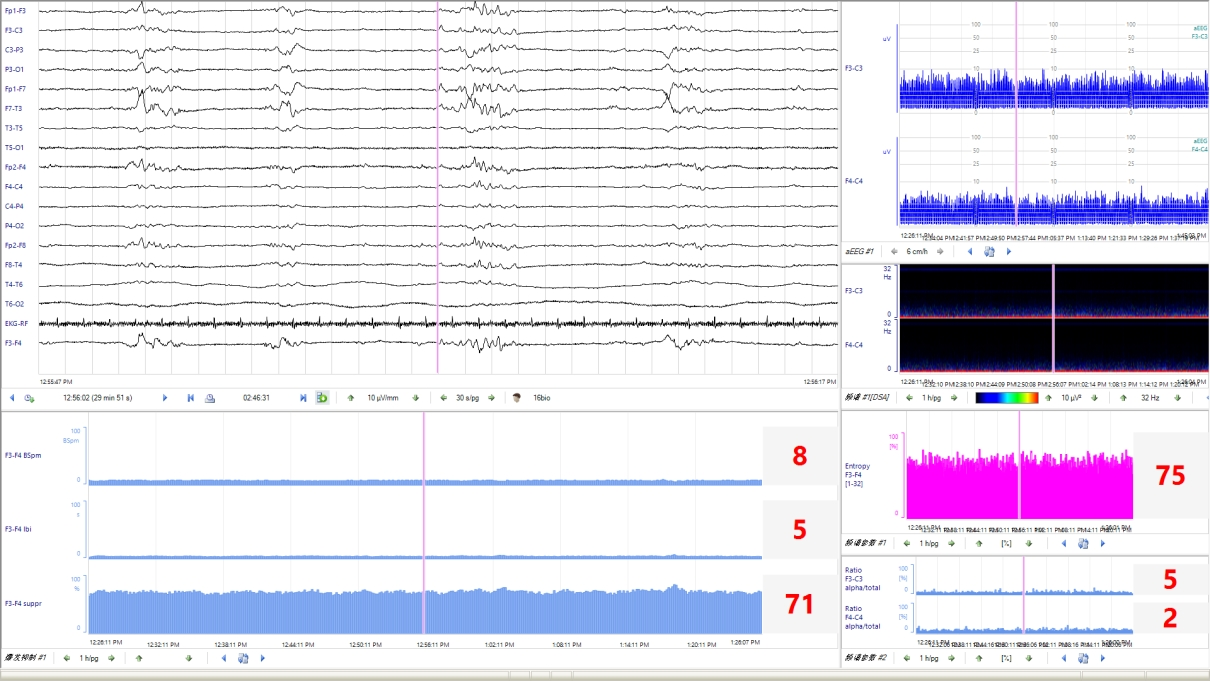

Q3:新生儿 aEEG的评价标准是什么?aEEG 主要从背景活动、睡眠周期及惊厥三方面进行评价和分类。aEEG的连续性亦被临床广泛关注。

睡眠周期未达到相应PMA成熟度的表现,则为睡眠周期落后于胎龄。3、惊厥发作(1) 单次发作:aEEG波谱带短暂中断,呈“驼峰”、“城垛”、“拱形”、“缺口”样改变。(2) 反复发作:aEEG出现多次上述改变。(3) 惊持续状态:既往认为发作时间超过30min或脑电图监测过程中异常放电占总监测时间的50%以上为惊持续状态。然而,为了减少惊厥发作时间及可能造成的神经损伤,aEEG表现为“锯齿”样波形时,即可根据不同的发作形式,在更短的时间窗内做出临床治疗决策。在KCNQ2基因致病性变异所致的发育及癫痫性脑病中,发作期aEEG呈现短暂上升后急剧下降(倒驼峰状)表现,aEEG中的短暂上升图形对应原始脑电图的发作期图形,急剧下降图形对应原始脑电图发作期后的广泛性电压衰减、甚至抑制图形。4、总体评估综上,近足月儿和足月儿可综合aEEG的背景活动、睡眠周期及有无惊厥进行总体评估,分为正常、轻度异常和重度异常,aEEG异常提示患儿可能存在脑损伤或脑发育成熟度延迟。Q4:早产儿 aEEG的特点及其临床意义?早产儿aEEG的背景活动、睡眠周期随胎龄而变化。随胎龄的增加,振幅上边界逐渐降低,下边界逐渐升高;睡眠周期也从最早的无法辨认到出现成熟的正弦样变化;aEEG图形由不连续图形过渡为连续图形。见表1。通过aEEG图形变化可定性评价早产儿的脑发育情况。

Q5:aEEG诊断新生儿脑病及判断神经发育预后的价值?aEEG可用于辅助诊断出生后6h内缺氧缺血性脑病(hypoxic-ischemic encephalopathy,HIE)的严重程度。窒息新生儿出生后6h内aEEG背景活动异常可作为开始亚低温治疗的准入标准,建议至少监测30min。但是不能因aEEG背景活动正常将HIE新生儿排除在亚低温治疗之外,需进一步结合临床。建议在新生儿HIE亚低温治疗和复温期间进行连续aEEG监测,或者每天监测一次、每次至少2h,以评价脑功能和疾病转归。aEEG对预测HIE新生儿预后具有一定的敏感性和特异性,应重点关注aEEG背景活动及其动态变化趋势。行亚低温治疗的患儿,48h aEEG的背景活动和睡眠周期很关键,治疗48h后aEEG正常的患儿预后好。复温时无睡眠周期与预后不良相关未行/无条件行亚低温治疗的患儿,6h aEEG正常的患儿神经发育预后好;36h有睡眠周期的患儿神经发育预后好。持续的背景活动异常和缺乏睡眠周期与2岁时发育迟滞相关。代谢性脑病患儿中,70% aEEG背景活动异常,60%出现癫痫发作。Q6:如何应用aEEG筛查和准确识别新生儿惊厥?新生儿惊厥的临床表现不典型,部分惊厥可只有电发作而无临床表现,故可能因漏诊而延误治疗,从而引起或加重脑损伤。另外,部分抗惊厥发作药物有潜在的神经毒性。故通过持续的床旁脑电监测,可以减少漏诊、避免过度诊断,并指导抗惊厥发作药物的精准使用。aEEG对惊厥监测的优点是时效性强,可以直接、快速地在床旁开展,且可长时间监测,常用于新生儿惊厥的筛查、疗效监测和评估。但由于aEEG为时间压缩图形,可能会漏掉振幅低、发作时间短(<30s)和起始部位距离监测电极远的惊厥。缺乏发作期脑电图的时空演变图形(通常在多通道脑电图中可以看到)是aEEG的另一个重要限制,如结合有视频记录的原始脑电图,aEEG对于惊判读的敏感度和特异度可分别达到76%和85%左右。早产儿惊厥的诊断在临床上更为棘手,由于早产儿惊厥时临床症状相对不明显或不典型,发作期脑电活动持续时间相对短,振幅低,扩散范围小,发作期的aEEG图形常不易识别;新生儿重症监护室中呼吸机的使用和各类操作干扰也可造成疑似惊厥发作图形而误诊。因此aEEG中出现任何可疑的上下边界短暂改变时,均需通过对比同期的原始脑电图加以证实。视频脑电图(video-electrencephalography,VEEG)是新生儿惊厥诊断的金标准。没有多导VEEG的前提下,aEEG可以用于新生儿惊厥发作的监测,但是需要同时分析原始脑电图,最大限度避免伪差干扰导致的误诊。当临床高度怀疑有惊厥发作而aEEG未监测到痫性放电时,建议增加导联数量,使用8导以上带有视频监测的aEEG设备。有条件的医院应进行长程vEEG监测。使用aEEG进行新生儿惊厥诊断时,建议至少有一次vEEG检查,并与神经电生理专家密切合作。